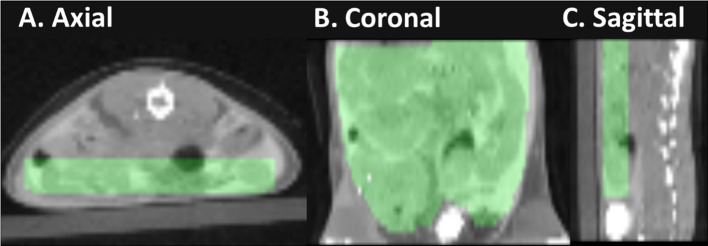

The monoclonal antibody bezlotoxumab, was radiolabeled with [125I]I for in vitro characterization and with [89Zr]Zr for in vivo PET imaging, resulting in high radiochemical yields (75.36 ± 4.11% for [125I]I and 71.58 ± 8.19% for [89Zr]Zr) and purities (> 99.99% in both cases), with stable binding properties. PET/CT imaging 48 h post-infection in an animal model of CDI (C57BL/6 mice and ribotype 027 strain) demonstrated specific accumulation of [89Zr]Zr-DFO-Beztxab in the colon and cecum of infected mice, thus making it possible to distinguish CDI from dysbiosis without specific C. difficile infection and healthy controls. Findings were confirmed by PET-based quantification and ex vivo biodistribution.